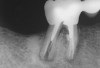

The length of the post space should be at least one half the root length while still maintaining the apical seal of gutta-percha.3,7,37 It is recommended that gutta-percha be removed using a heated endodontic instrument and/or canal-safe Gates-Glidden drills. Aggressive use of inflexible post drills within the root canal can lead to perforation of the canal with subsequent negative consequences on the survivability of the tooth (Figure 2).3,7 This author recommends that the post drills provided by manufacturers be used more as a canal-sizing instrument than for post preparation within the canal. The rationale for using the post drill in this manner assures that the root canal is not overprepared with the potential of perforation of the root canal. It is important when removing the gutta-percha that the length of the root canal be known so that whichever technique is used to remove the gutta-percha, the instrument can be marked to the length of root canal preparation desired. In the case of a rotary instrument or a heated instrument, an endodontic stopper can be placed on the instrument to the length desired (Figure 3). After making the post space, it is advisable to make a radiograph of that tooth to verify the length of the post space and the removal of the gutta-percha (Figure 4).

Figure 2  Post space created off-line from root canal creating a root perforation.

Figure 2

Figure 4  Take verifying radiographs to check on gutta- percha removal and length of post space desired.

Figure 4